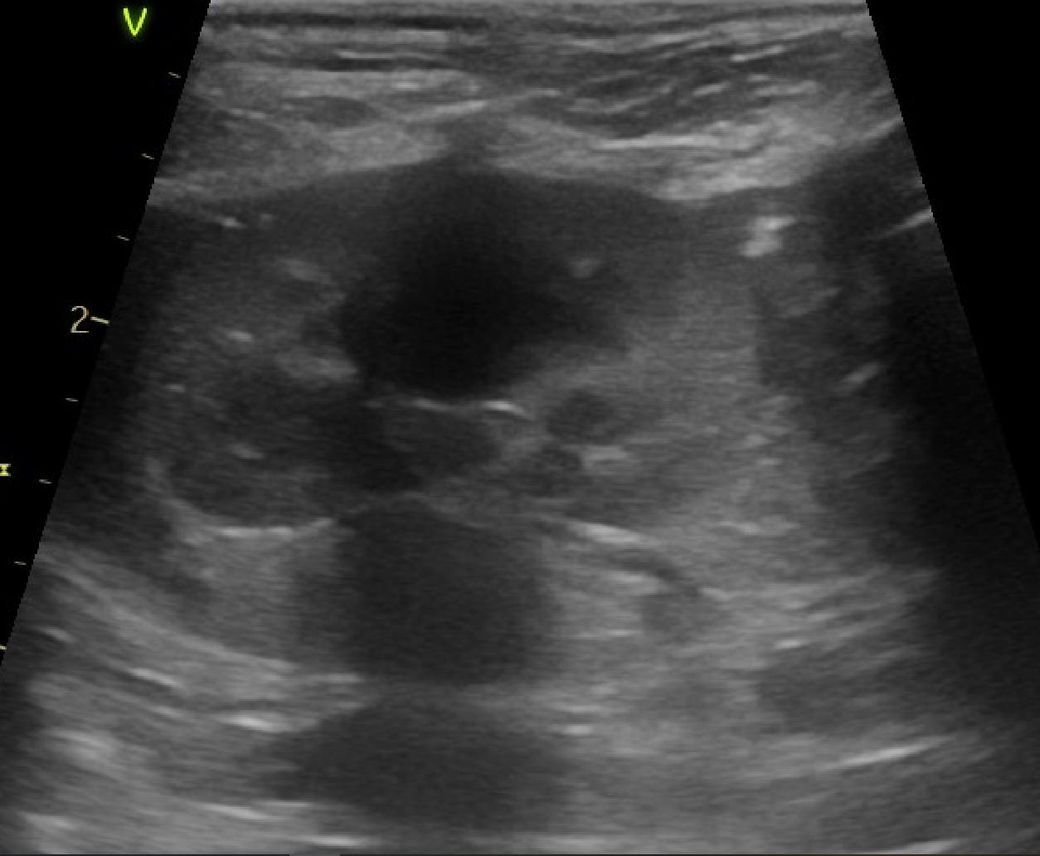

강아지 신장결석 칼슘옥살 스트루바이트 둘중 어느것 같아보이는지요?

강아지 신장결석 칼슘옥살 스트루바이트 둘중 어느것 같아보이는지요? 그냥 보시기에 만약에 판별이 가능하다면 알려주심 정말 감사하겠습니다. 병원만 3곳 다녔고 소변검사에 방광천자 제외하고 전부다 해봤는데 현재 6개월이 넘어갔는데 무슨 결석인지도 모르는 상태고 결석 크기는 신장 양쪽에 점점 커지고 있는 상황이라 이대로는 가만 있을수가 없어서 이렇게나마 질문글 올립니다.. 부디 알려주심 정말 한생명 살리는샘치고 정말 감사하겟습니다.

안녕하세요. 박창민 수의사입니다. 초음파 검사로 결석이 있는지, 위치나 크기, 개수, 형태 같은 정보는 확인할 수 있지만 결석의 정확한 종류나 성분까지는 알 수 없으며, 결석의 성분을 확인하려면 결석을 직접 채취해 분석하거나 소변 검사, X-ray, CT 등의 추가 검사가 필요합니다. 감사합니다.